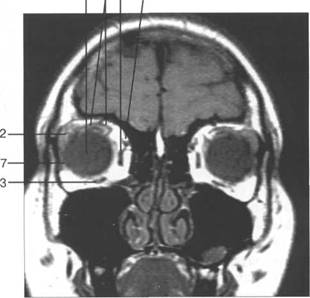

орбитальная клетчатка 4 3

(corpus adiposum orbitale).

HU), каплив 121h711b ают контрастный препарат. Толщина хнюю прямую мышцу видно плохо, обычно ее изображение слив 121h711b ается с изображением мыш­

На КТ-изображениях глазное яблоко имеет шаровидную структуру, четко выраженную обо­лочку, внутри его определяется хрусталик эллиптической формы размером 4x9 мм, плотностью

четлив 121h711b о дифференцировать зрительный нерв и глазодвигательные мышцы (рис. 2.16, 2.17).